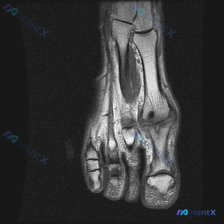

看到一个典型的前足MRI病例,整理了影像资料和分析思路,跟大家分享一下。 病例影像基本信息 这是一张前足区域的冠状位T1加权MRI,图像质量清晰,聚焦于跖骨及跖趾关节区域: 1. 骨髓信号:跖骨骨干及近端骨髓为正常脂肪高信号 2. 阳性发现:第2跖骨头可见一类圆形局灶性低信号区,边界相对清晰 3....